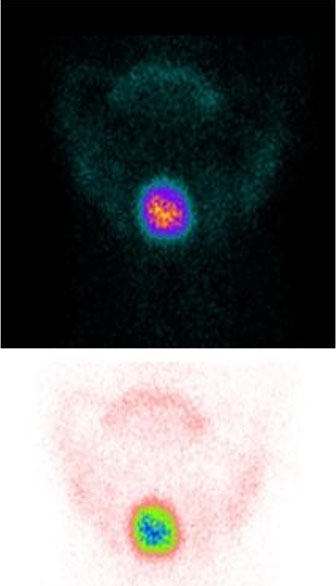

Fiber optic flexible indirect laryngoscopy (FIL) revealed a mass at the base of the tongue, thus arising the diagnostic suspicion of LT. The diagnosis was confirmed by an endocrine surgeon-performed neck ultrasound that revealed a 34 mm solid hypoechoic slightly heterogeneous suprahyoid nodular structure compatible with thyroid tissue. No thyroid parenchyma was detectable in the usual thyroid site. No pathologic lymph nodes were detectable (Figure 1).

Figure 1: Ultrasound scan of the suprahyoid nodular formation.